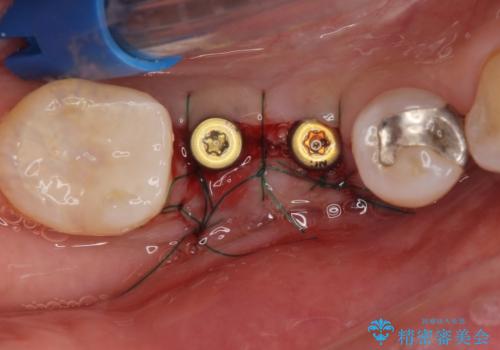

無事インプラントが入りました。

インプラント治療をしてもメンテナンスを怠っているとインプラント歯周炎になるリスクがあがるのでメンテナンスをお勧めします。

- 抜歯、歯槽堤保存術・11万円 インプラント体、アバット、仮歯、ジルコニアクラウン・42.9万円×2 骨造成・5.5万円 e-maxインレー・7.7万円 費用は治療当時の料金となります